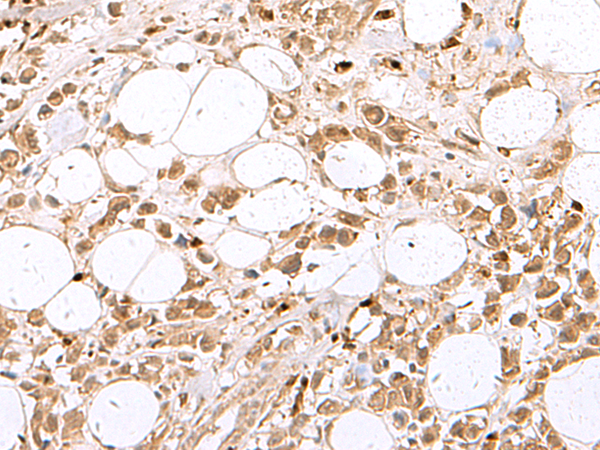

分类: 科研抗体货号: P10094别名: MKPX; PYST2应用: IHC反应种属: Human, Mouse, Rat